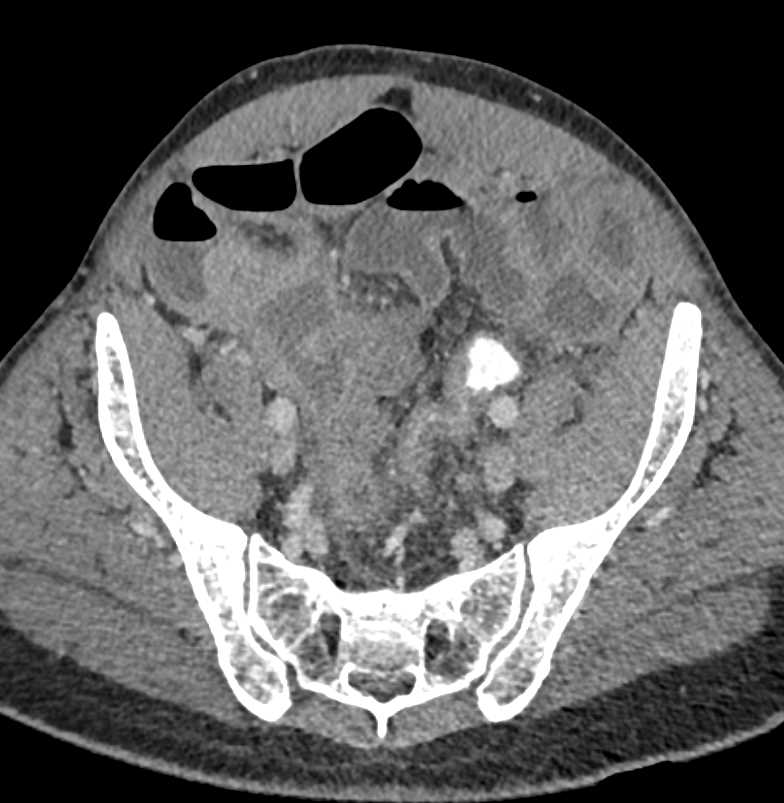

Small Bowel Carcinoma with Carcinomatosis